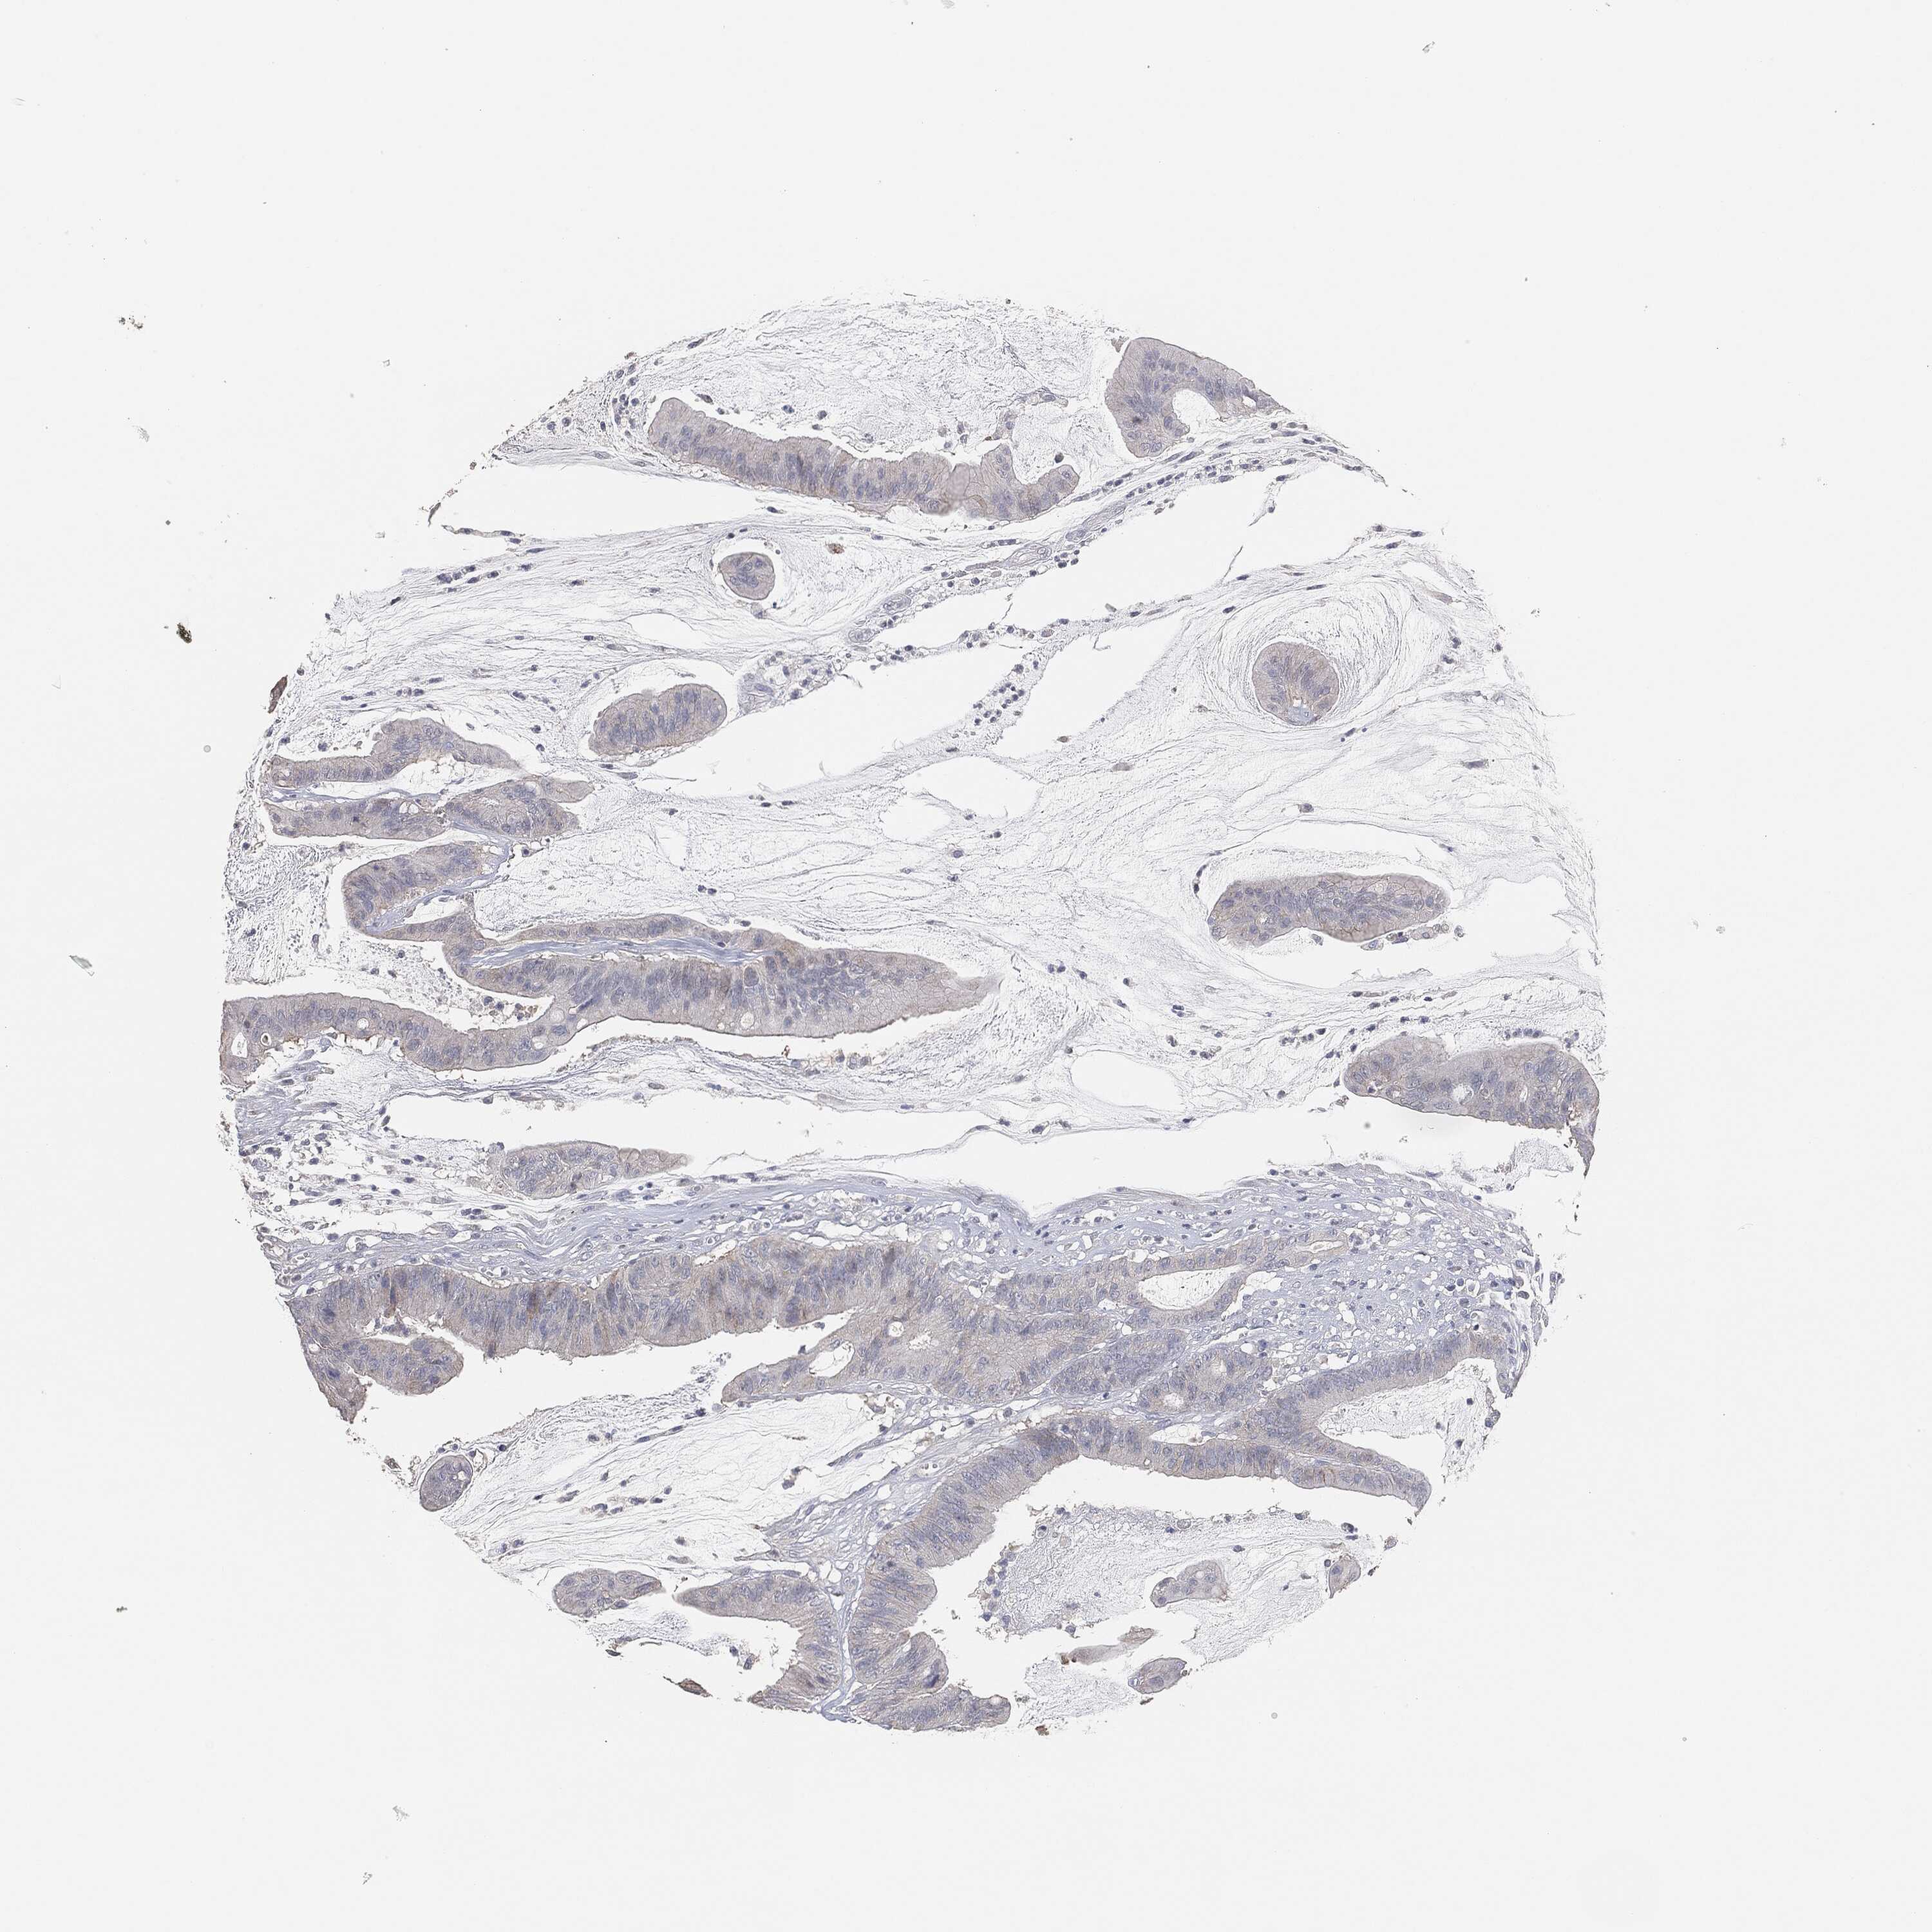

CANCER COLORECTAL CANCER Show tissue menu

Colorectal cancer

Human cancer

Colon adenocarcinoma